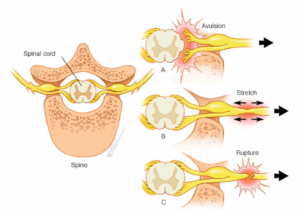

Brachial plexus injury

The brachial plexus is the group of nerves that sends signals from the spinal cord to the shoulder, arm and hand. A brachial plexus injury happens when these nerves are stretched, squeezed together, or in the most serious cases, ripped apart or torn away from the spinal cord.